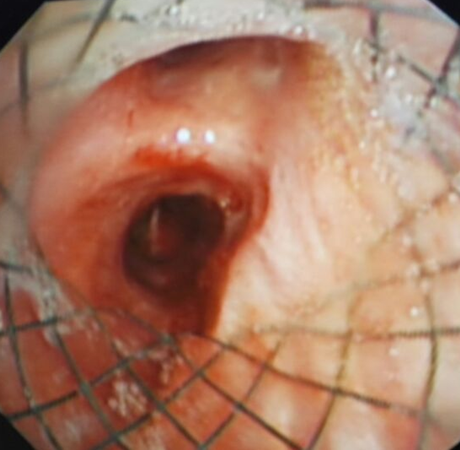

术后支气管镜检查:左侧气管瘘口已由带膜支架完全封堵。而右侧支气管系统通畅,维持患者通气功能。

术后患者胸腔闭式引流管未在有气体逸出,同时胸腔感染逐渐控制。

远期如残端闭合后,可于支气管镜下取出支架,使支气管胸膜瘘得到治愈。